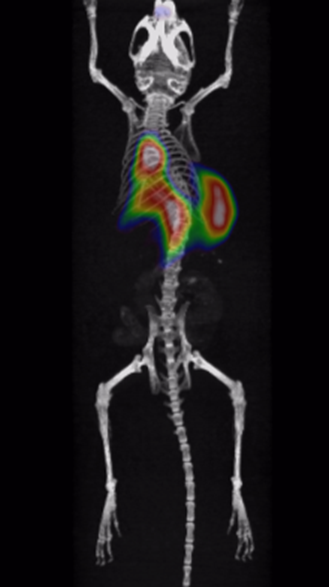

Through quality and process explorations with Zr-89-marked antibody conjugates, highly emissive-pure radiodiagnostic drug molecules are obtained and supplied for preclinical animal imaging and biodistribution studies, as well as subsequent IIT imaging in the clinic.

Rapid validation of Zr-89-marked antibodies

Fast lesion cumulation, most efficient distribution and high targeting ability for xenotransplanted tumor models.